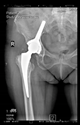

The guiding wire was inserted and controlled with fluoroscopy flashes (Figure 4). The drilling and reaming were carried out in accordance with the recommendations:

Figure 4.

The biocompatible aiming device after insertion of the guiding wire.

The direction of the cup stem was determined by the guide wire. The aiming device was needed to introduce this wire. After removing the aiming device, the next step was the drilling. Since a cannulated drill bit was used, the previously installed wire could guide the process. A self-positioning reaming tool was then used in the drilled channel. In the prepared cavity, the cup was fitted perfectly. Of the two stemmed cups available to us, the McMinn cup (Waldemar Link, Hamburg, Germany) had the simpler geometry and was therefore chosen. The stemmed cup was inserted according to the manufacturer’s recommendation. In the presence of a significant bone defect, a synthetic bone graft may be impacted for substitution.

The radiological examination allowed us to verify the close bone-to-implant contact and the unchanged position of the implant during follow-up.

In all the cases operated with the above-described targeting procedure, the stems of the cups remained between the cortical bone surfaces without perforation of the linea terminalis, as shown by postoperative radiographs. There were no complicated surgical situations. In 16 cases, the wound healings were uneventful, and the hips were able to bear weight again after postoperative rehabilitation.